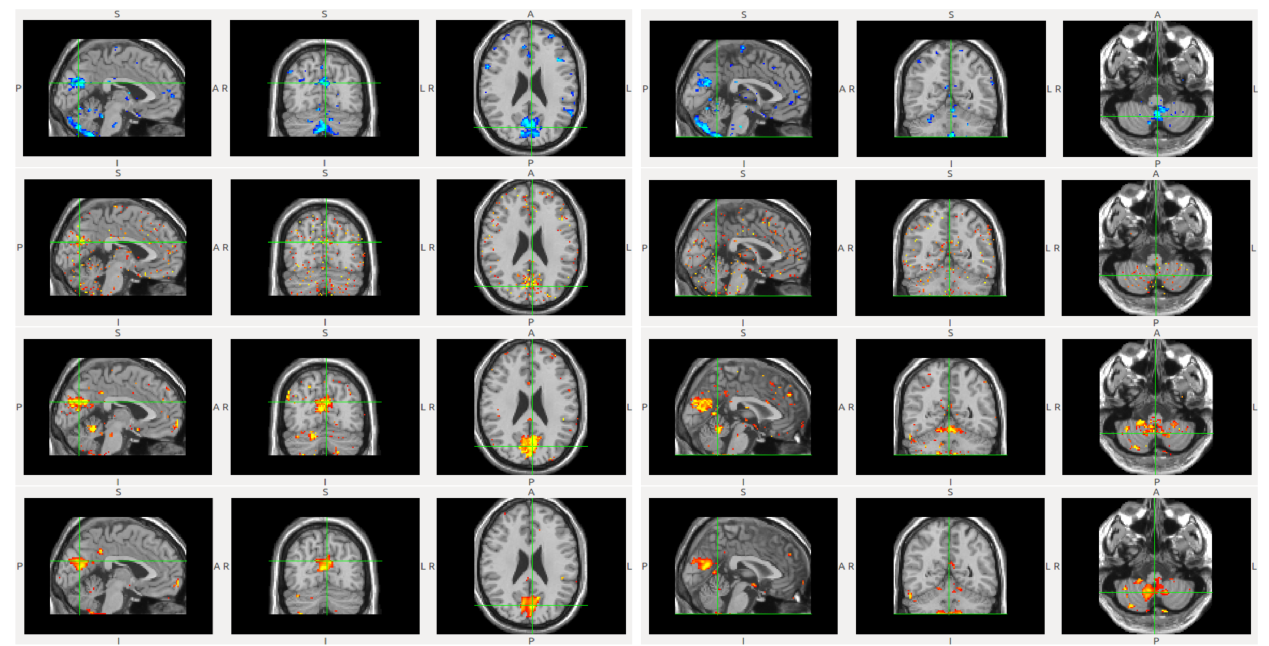

Comparison of statistical group analysis results on cuneus (left column) and cerebellum (right column) using FDG-PET scans with respect to APOE genotype. First row: Using properly registered scans (baseline), Second row: Using imperfectly registered scans (10% noise level), Third row: Our results on imperfectly registered scans (10% noise level), Fourth row: Our results on imperfectly registered scans (GRF noise).